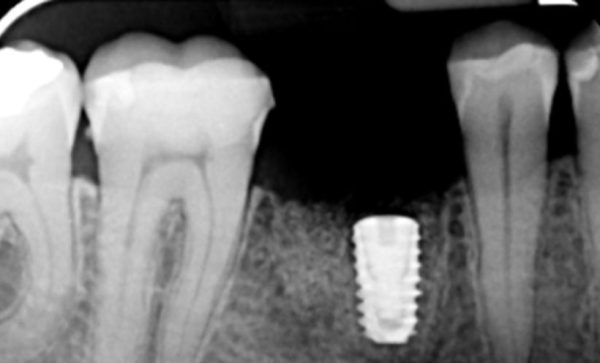

I have been a patient of Dr Verma for 8 years, my treatment has included crowns and an implant. Treatment plans and options are explained to me clearly, my concerns and anxieties are allieviated without hurry or pressure in a gentle and reassuring way. I feel my patient satisfaction is valued.

Sukal has been my dentist for many years, from simple check ups to a dental implant! I have always felt comfortable in the dentist chair and happily watched the TV on the ceiling while work is done on my teeth and never once felt any pain and always felt comfortable. I would never go anywhere else! Thank you all for being kind, caring and helpful at all times :-) Sarah Galloway